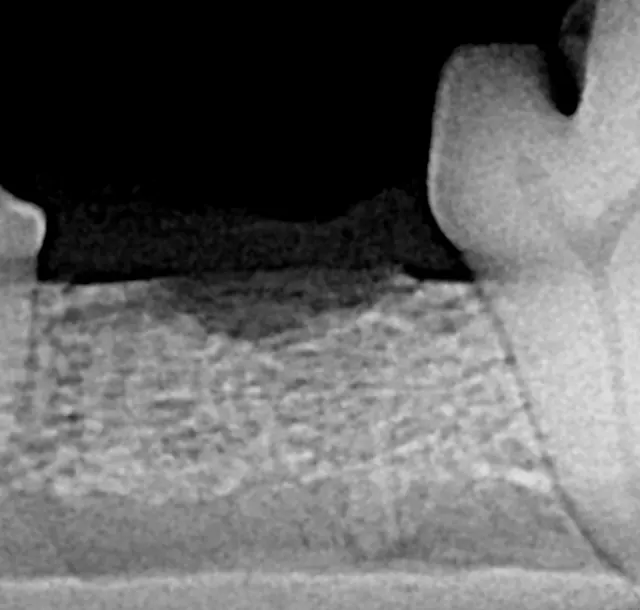

Intraoral radiograph of the left mandibular fourth premolar; the distal root is affected by external resorption that has not extended into the oral cavity.